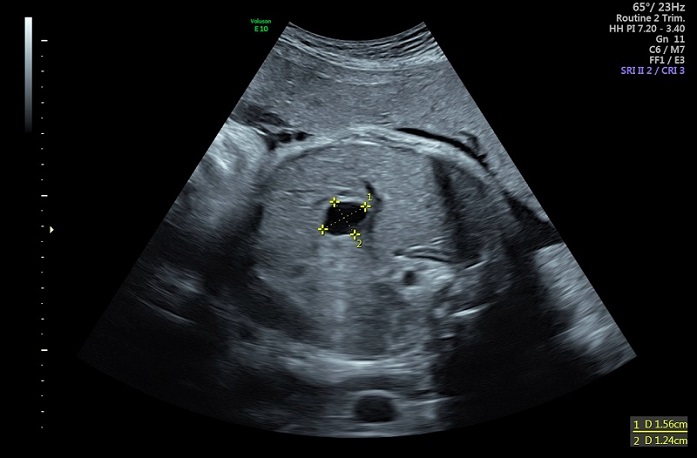

Para completar el estudio, se solicitó una analítica sanguínea, en la que no se objetivaron alteraciones en la función hepática, con albúmina, glucosa y coagulación normal, y sin colestasis ni hipertransaminasemia. La alfafetoproteína era de 150 ng/ml. A los 4 meses de vida, la ecografía de control no mostró cambios significativos con respecto a las previas (Figura 3).

| Figura 3. Quiste hepático congénito. Ecografía posnatal de control. En el segmento IV continúa visualizándose un quiste simple unilocular de pared fina, de diámetros similares al estudio previo (25 x 17 mm en sus ejes TR x AP), actualmente con un pequeño nivel ecogénico declive en su interior |